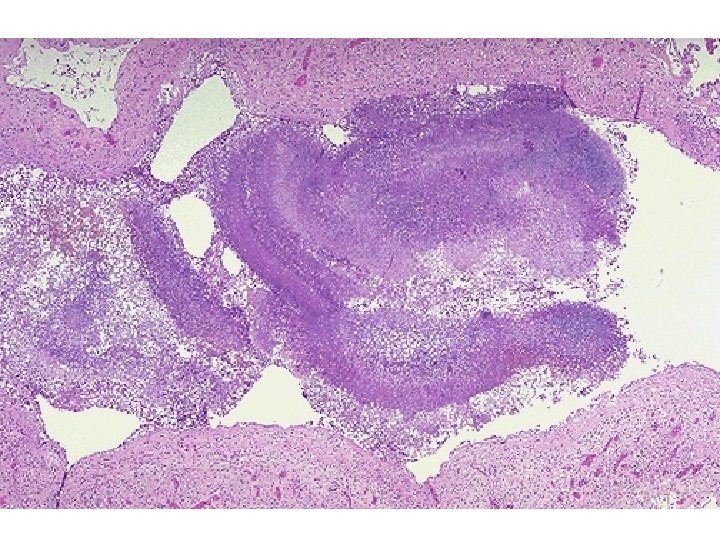

INFECÇÃO: MORTE CELULAR AGUDA E DESTRUIÇÃO TECIDUAL Muitas bactérias produzem toxinas ou enzimas que danificam as células e os tecidos. As enzimas incluem proteases, elastases, colagenases e várias citotoxinas. As próprias bactérias e as células lesadas liberam substâncias quimiotáticas que atraem neutrófilos - polimorfonucleares para o tecido inflamado. Ativação da cascata do sistema complemento através de endotoxinas bacterianas é um gerador potente da inflamação tecidual aguda. Uma vez que os neutrófilos entram no tecido, eles também contribuem para o dano do tecido porque eles produzem proteases adicionais na tentativa de destruir os invasores bacterianos. Caso ilustrativo: meningite por Streptococcus agalactiae (Group B beta hemolytic streptococcus)